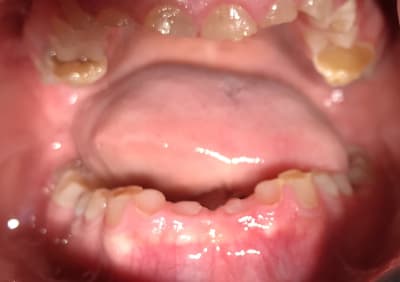

Bonjour je suis lenovo ici . Quelqu’un pourrait-il me donner toutes les étapes pour faire ce cas ? Que faut-il faire précisément ? Le patient n’a pas de contraintes financières. Pas de lésions apicales. Uniquement des usures de dents.

la photo peut tromper mais il semble être en clII,2 en plus.

Je que je trouve impressionnant et peut être le plus complexe à gérer c'est cette bascule du pré maxillaire.

Les photos ne sont pas dingues, mais les usures semblent très majoritairement antérieures. Pourquoi?

Et le fait que 17 18 27 28 semblent intactes alors qu'apparemment il y a des antagonistes intactes aussi